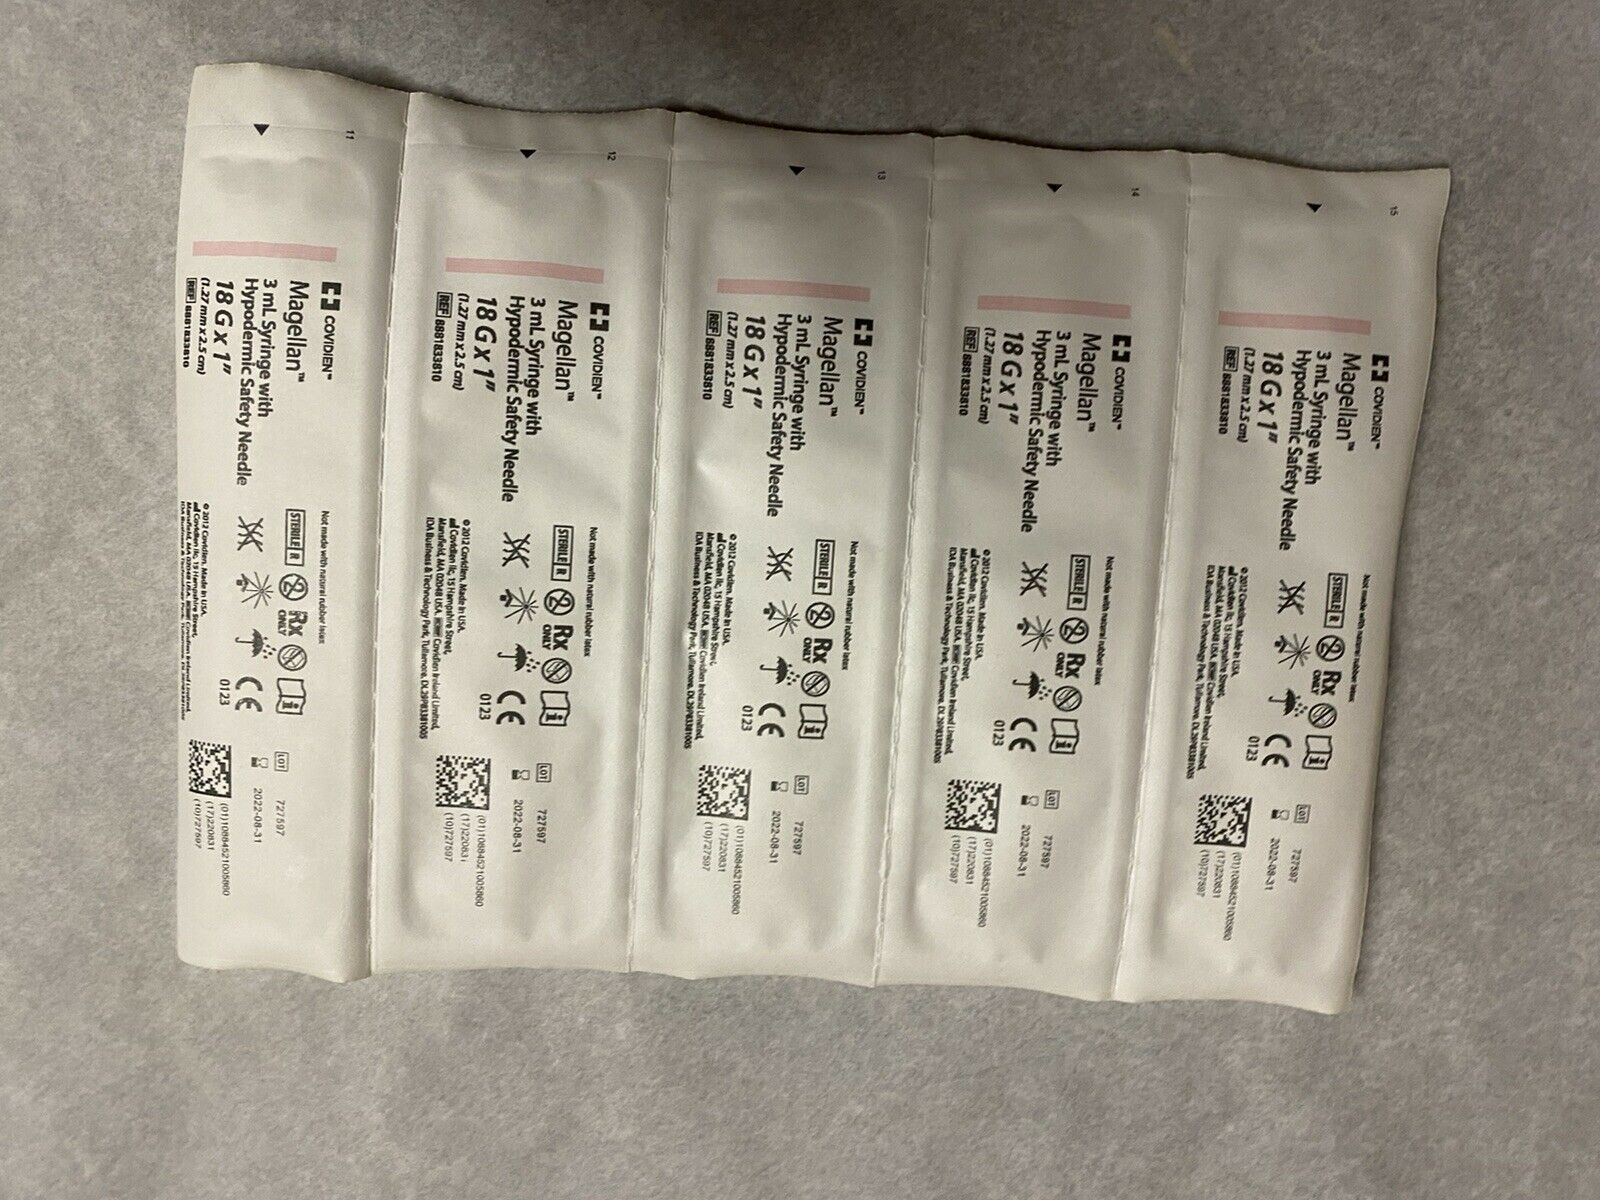

Save $ 5.40

DIAGNOSTIC ULTRASOUND MACHINES FOR SALE

BRAND NEW 3ml(3cc)1 box of 50 Syringes

Sale price$ 24.59

Regular price$ 29.99